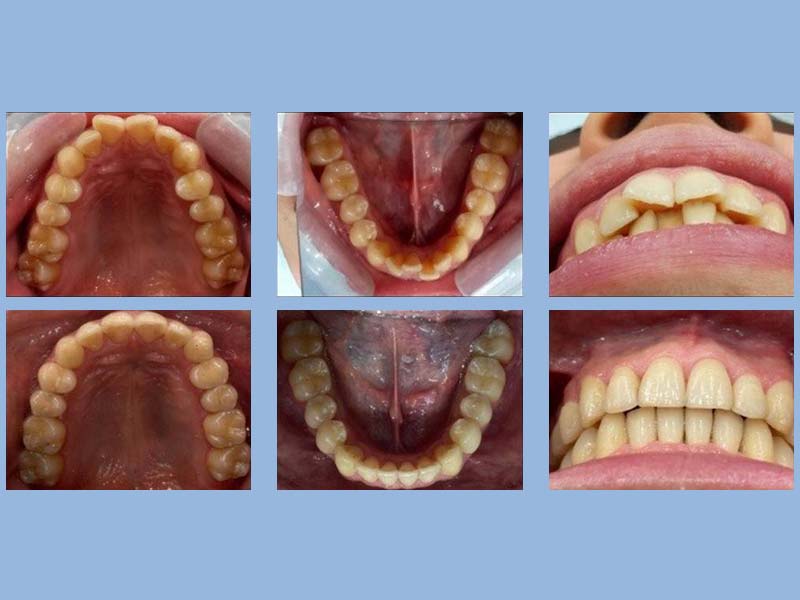

余先生 (20歲) 矯正完成

狀態 : 第二套完成照、暴牙、牙齒擠、沒拔牙